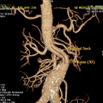

Aorta Bone VR

显示腹部主动脉及其主要分支血管与骨骼的相应关系